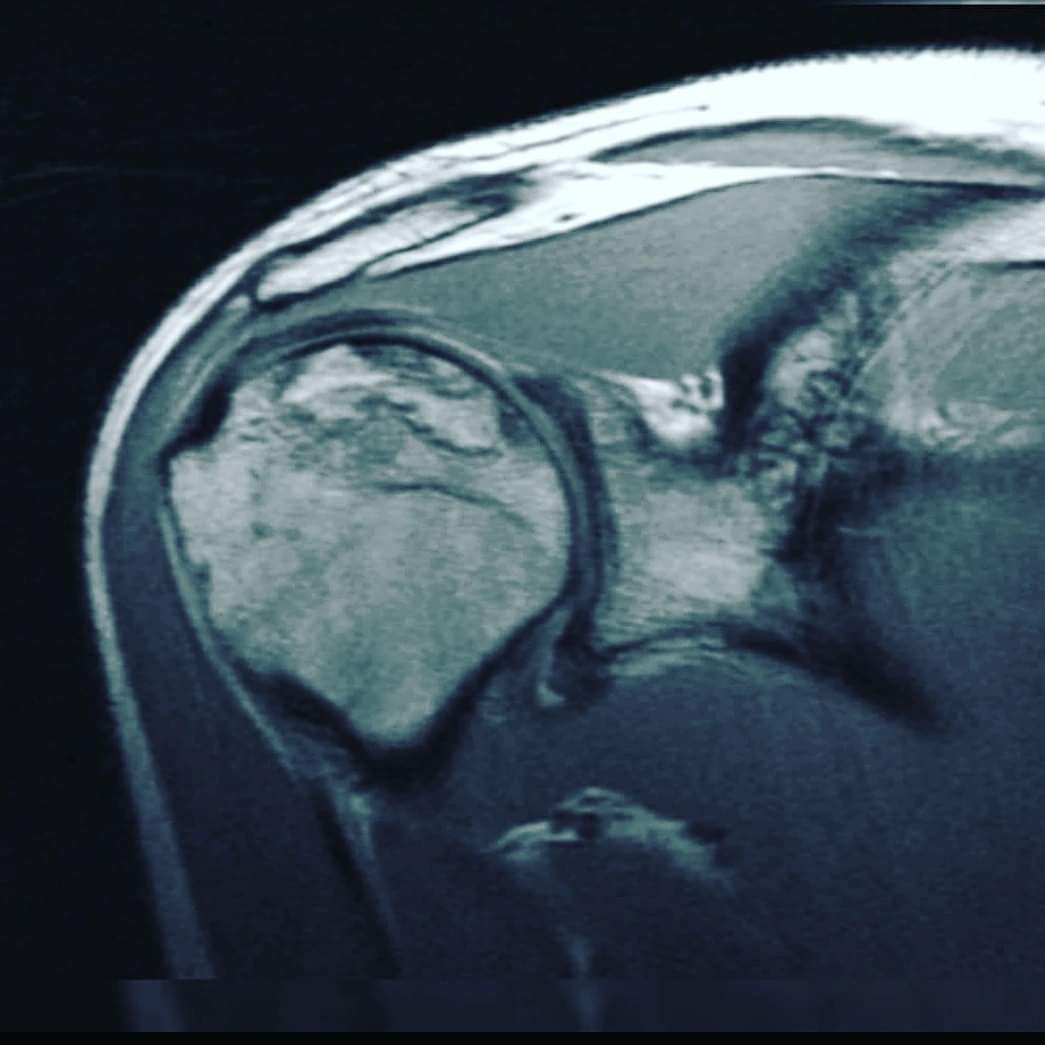

На цьому знімку плечового суглоба - деформація кісткової частини 4 ступіню. Зарадити нічим вже не можна. Не чекайте цього! Виправити, відновити, покращити функцію суглоба, хребта, враженого навантаженнями, чи віковими змінами, пов'язаними зі старінням - МОЖЛИВО! Гарна новина в тому, що Ви, при наявності будь-яких проблем с хребтом та суглобами, маєте змогу зараз, вчасно звернутись до лікаря-фахівця, який зупинить незворотні зміни. Запропонує метод відновлення, який, без перебільшення може врятувати Ваш хребет, чи суглоб, від заміни хірургом на штучний...